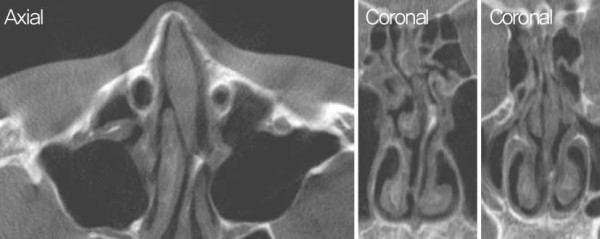

![]()

수술 후 수술장 사진. 수술 후 사비 및 비공 비대칭, 콧대의 불규칙성이 개선된

모습이 확인된다

이 환자의 경우, cleft nose가 있음에도 불구하고 비익 연골 기저부의 변형이 심하지 않아 alar base surgery 는 별도로 시행하지 않았다. Cleft nose의 경우 일반적 으로 다음과 같은 특징이 나타난다. ① 비중격연골의 만곡 방향이 뼈와 연골에서 서로 다르게 형성된다. ② Nasal spine이 병변 반대쪽으로 이동되어 있는 경우, 병변이 있는 쪽의 상악뼈에서 결손이 관찰된다. ③ 비익 연골의 비대칭으로 인해 병변이 있는 쪽의 비익연골이 퍼져 있으며, 바닥이 낮게 형성된다. 구조적 특징을 고려하여 다음과 같은 교정 방법을 적용 하면 좋은 결과를 기대할 수도 있다. ① 비중격연골을 병변 쪽으로 이동시켜 연골부와 골부의 만곡을 일치시 킨 후, 강력한 이식술을 시행하여 교정한다. ② 병변 기 저부의 뼈 결손 부위에 연골을 이식하여 구조적 안정성 을 확보한다. ③ 비익연골의 비대칭을 교정하기 위해 비 중격연장술 및 alar base surgery를 시행한다. 이와 같은 접근 방식을 통해 보다 균형 잡힌 코의 형태를 얻 을 수 있으며, 기능적인 개선도 기대할 수 있다.